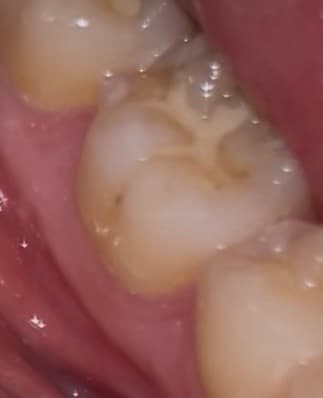

이정도 치아 깨진거 치료 받아야할까요? +충치

딱딱한거 씹다가 깨졌는데

가끔 뜨거운거 먹었을때시큰거리는 정도고

일상생활할때 불편한건 없습니다

1. 깨진거 치료 받아야할까요?

2. 저정도 깨짐은 어떻게 치료하나요? 아플까요?

2. 옆면에 있는 충치 상태도 좀 봐주세요 ㅠㅠ

사진으로 봤을 경우에 치아가 깨진 것보다 부분 부분 충치가 보이고 있습니다. 충치가 있는 부분엔 이물질이 남아 있게 되어 충치가 진행될 수 있으니 충치가 있는 부분은 치료를 해주는 것이 좋습니다.

깨진 정도가 크진 않으나 한번 깨졌던 치아는 그 부위가 씹을때 힘이 강하게 가해진다는 것이므로 또 추가적으로 깨질 우려가 큽니다. 전반적으로 상태 보고 레진으로 떼우거나 아니면 크라운을 씌워주면 좋을 것 같습니다.

옆면 충치 큰 편은 아닙니다.